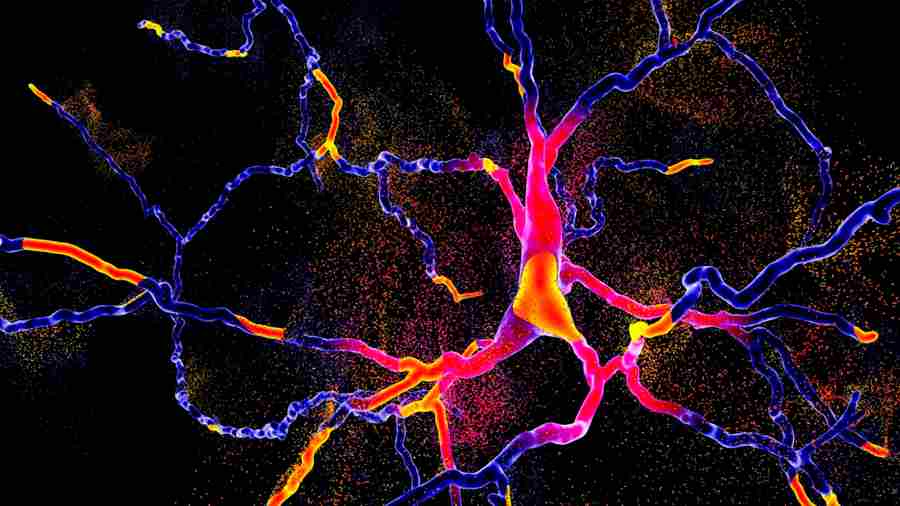

Un nuevo estudio realizado por científicos del Instituto Buck para la Investigación del Envejecimiento ha revelado un factor sorprendente en la lucha contra el Alzheimer y otras formas de demencia: el metabolismo cerebral del azúcar. Publicado en Nature Metabolism , la investigación revela cómo la descomposición del glucógeno (una forma almacenada de glucosa) en las neuronas puede proteger al cerebro de la acumulación de proteínas tóxicas y la degeneración.

El glucógeno se considera generalmente una fuente de energía de reserva almacenada en el hígado y los músculos. Si bien también existen pequeñas cantidades en el cerebro, en particular en las células de sostén llamadas astrocitos, su papel en las neur...